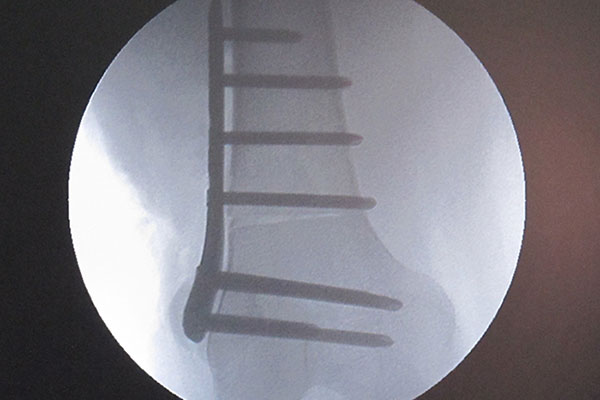

Varising Derotational Distal Femoral Osteotomy